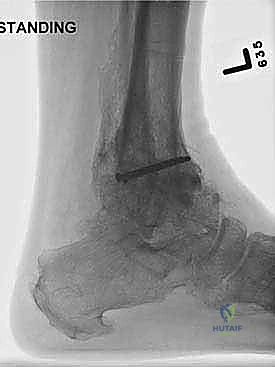

Weight-bearing anteroposterior (AP), lateral, and mortise views of the ankle

10. TECH FIG 4 • A-C. A 55-year-old man with chronic instability and posttraumatic arthritis. A. AP view with comparison to contralateral ankle. B. Mortise view. C. Lateral view. There is considerable anterior translation of the talus from the ankle mortise. (continued)

Follow-up radiographs ( TECH FIG 4J-N )

14. TECH FIG 4 • (continued) J-N. Postoperative weight-bearing radiographs of example patient with traditional screw fixation and supplemental anterior plate. J. AP radiograph. K. Mortise view. L. Lateral view (talus is reduced under tibial axis). M. Dorsiflexion view. N. Plantarflexion view. The patient lacks some hindfoot compensation for dorsiflexion and plantarflexion.